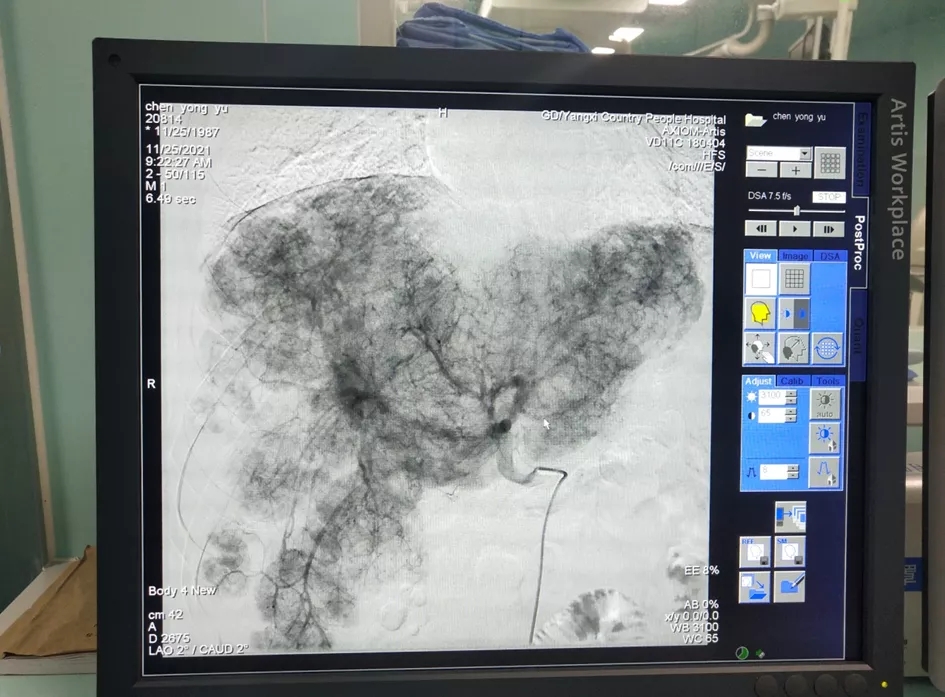

阳西总医院人民医院肿瘤科成功为患者进行了肝动脉灌注化疗(HAIC)。HAIC疗法经股动脉将微导管置于肝肿瘤分支血管,通过微导管将抗肿瘤药物直接送达肝内肿瘤血管达到治疗目的。经过1个周期的治疗,患者肝部肿瘤较前明显缩小,对胃的压迫减轻,已能正常进食,腹痛腹胀消失,再经过2个周期的HAIC治疗后,肝内巨大肿瘤染色基本消退。